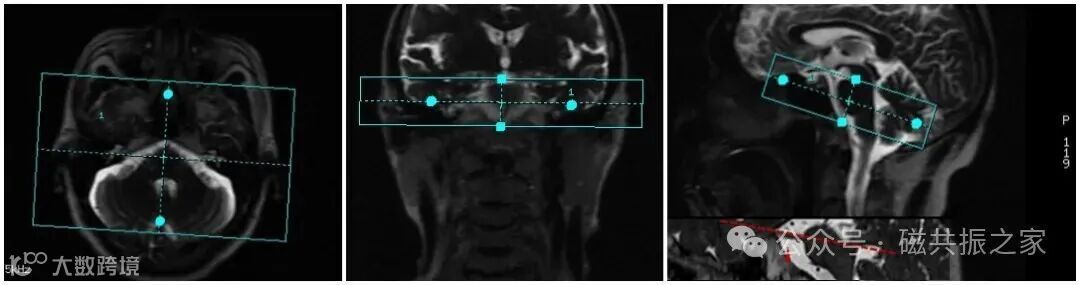

通常采用轴位的扫描方式,其角度与目标神经的大体走形平行。如上图△所示,行三叉神经颅内段的扫描中,其扫描基线应与其神经的大体走形一致。

根据方位角度的需求对目标神经进行后重建处理,如上图△,展示的为对单侧面、听神经进行处理。